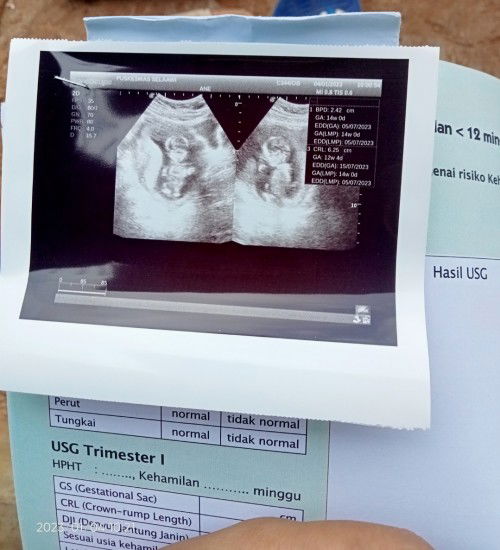

Hay assalamualaikum mau tanya kalo cara baca BBj di USG gimana ya

itu cuma dikasih 1 kah Bun? biasanya ada 2, itu juga gak di tulis BBJ nya entah karna masih terlalu kecil belum ada BBJ masih pake hitungan cm

aku pas 12w diitung berdasarkan panjang janin nya bund,pas 16w baru berdasarkan bbj nya.